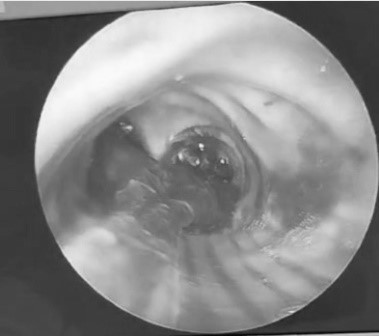

Se decidió la realización de una fibrobroncoscopía al pie de la cama, visualizando moldes endobronqueales hemáticos, los cuales obstruían de manera casi total el calibre de la vía aérea. Posterior a la realización del procedimiento, mejoró la ventilación y la oxigenación del paciente, este episodio vuelve a repetirse, por lo cuál se decidió procedimiento a través de fibrobronscopía rígida en quirófano. Se observa en Figura 1 la obstrucción generada en la vía aérea, y en la Figura 2 la extracción del molde.

Figura 1: Molde ubicado en carina

Se visualiza a través de fibro broncoscopia rígida el molde ubicado en carina obstruyendo ambos bronquios.